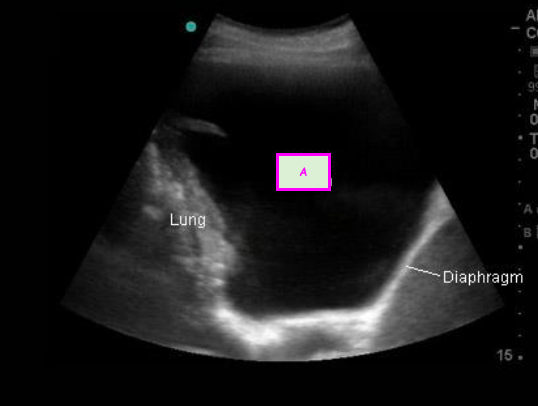

2

Q

This image shows an ultrasound of the lung.

What is A? [1]

A

Pleural effusion